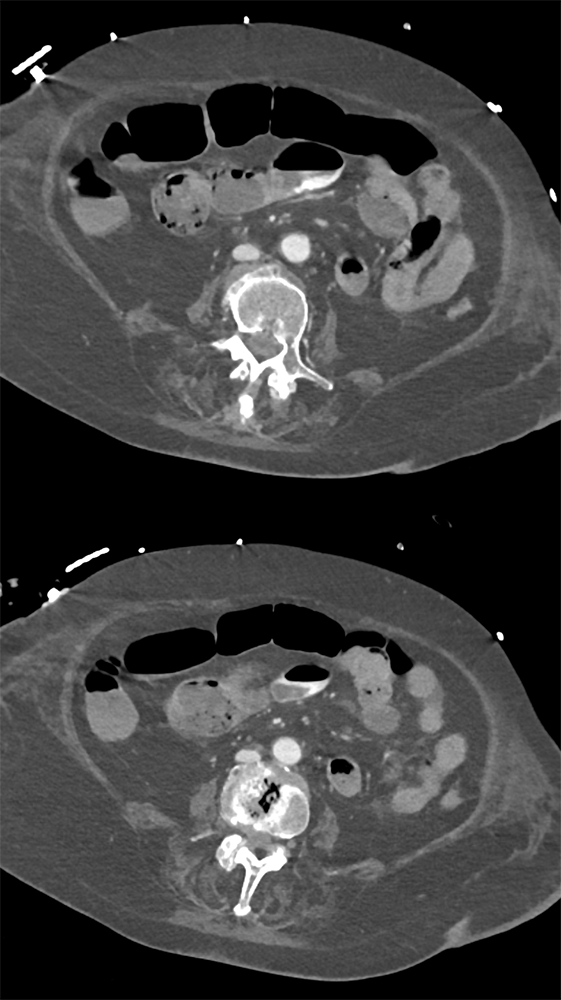

GIST Tumor Jejunum as the Cause of GI Bleeding ![]() |

![]() |

GI Bleed ![]() |